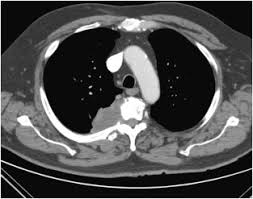

Signs And Symptoms Of Lung Cancer And Back Pain / Lower Back Pain And Cancer Symptoms Diagnosis And Treatment - Symptoms that may be more concerning for lung cancer include shoulder pain that's worse at night, pain that occurs at rest, and pain that's not associated with any loss of motion with activity.. It could therefore be a sign that your lung. Hemoptysis (coughing up blood) blood in spit. The main symptoms of lung cancer include: If lung cancer is diagnosed at an early stage, treatment is more likely to be successful. Sometimes you're hurting because the tumor inside the lung is pressing on nerves in the back or the spine.

Lung Cancer Symptoms Signs Of A Tumour Include Lower Back Pain When To See A Doctor Express Co Uk from cdn.images.express.co.uk Once lung cancer has spread beyond the lungs, it's generally not curable. A pancoast tumor is a type of lung cancer that grows in the upper part of your lung and spreads to your ribs, vertebrae in your spine, nerves, and blood vessels. According to the american cancer society, lung cancer is the second most common form of cancer in both men and women. Although a pancoast tumor is a lung tumor, it rarely causes symptoms that are typically related to the lungs (for example, cough and chest pain). The pain can also be a sign that your cancer has spread to your spine. The symptoms of back pain related to lung cancer are diverse and overlap significantly with back pain caused by other conditions. If lung cancer is diagnosed at an early stage, treatment is more likely to be successful. I saw a throat specialist who saw one of my two vocal cords was paralysed.

Signs And Symptoms Of Lung Cancer Everyday Health from images.everydayhealth.com The more common symptoms of lung cancer include: Moreover, back pain accompanied by other significant signs such as a persistent cough, shortness of breath, constant chest pain, unintentional weight loss, chronic fatigue, or the coughing up of blood may further support the likelihood of lung cancer. If lung cancer is diagnosed at an early stage, treatment is more likely to be successful. A pancoast tumor is a type of lung cancer that grows in the upper part of your lung and spreads to your ribs, vertebrae in your spine, nerves, and blood vessels. Hemoptysis (coughing up blood) blood in spit. Although a pancoast tumor is a lung tumor, it rarely causes symptoms that are typically related to the lungs (for example, cough and chest pain). Symptoms that may be more concerning for lung cancer include shoulder pain that's worse at night, pain that occurs at rest, and pain that's not associated with any loss of motion with activity. Bone pain (like pain in the back or hips) nervous system changes (such as headache, weakness or numbness of an arm or leg, dizziness, balance problems, or seizures), from cancer spread to the brain yellowing of the skin and eyes (jaundice), from cancer spread to the liver

It was andrew libby 's only symptom. Lung cancer symptoms include difficulty breathing, headaches, and persistent chest pain. Persistent coughing, coughing up blood or excess mucus, shortness of breath, and chest pain are all common signs of lung cancer. It could therefore be a sign that your lung. Headaches may be a sign that. Symptoms that may be more concerning for lung cancer include shoulder pain that's worse at night, pain that occurs at rest, and pain that's not associated with any loss of motion with activity. When lung cancer reaches its final stage, the patient will experience several physical and emotional changes. Most lung cancer patients are diagnosed from symptoms that result from the spread metastasis of the cancer to another site, such as the spine or liver. in fact, new and unexplained back pain is. If you think you have any of these symptoms go and see your doctor. Sometimes you're hurting because the tumor inside the lung is pressing on nerves in the back or the spine. The presence of these symptoms doesn't definitively mean you have lung cancer, though, as they can also be caused by other conditions. If lung cancer spreads to other parts of the body, it may cause: People who have lung cancer are unlikely to experience lower back pain as a symptom.